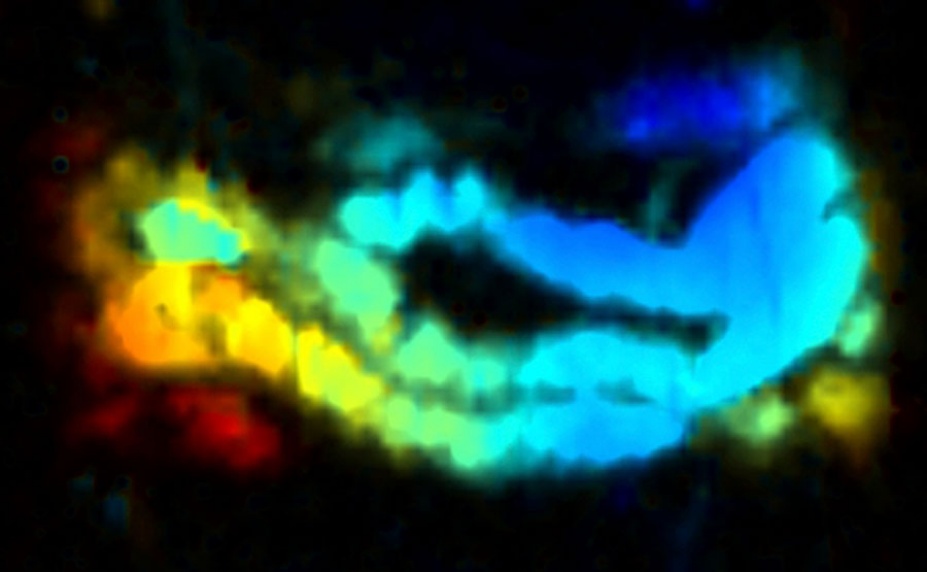

The combination of "nanojuice" and photoacoustic tomography illuminates the intestine of a mouse. (Credit: Jonathan Lovell)

In laboratory experiments performed with mice, the researchers administered the nanojuice orally. They then used photoacoustic tomography (PAT), which is pulsed laser lights that generate pressure waves that, when measured, provide a real-time and more nuanced view of the small intestine.